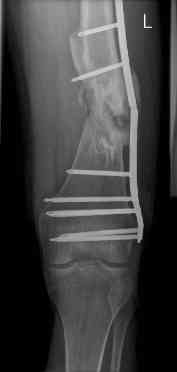

16 yr old boy, high energy motorcycle trauma trauma in July 2005 with:

- hip dislocation + acetabular fracture L

- distal femoral fracture L

- tibial shaft fracture L

- metatarsal fractures L

july 05: LISS femur, LCP plate tibia, double recon. plate post. acetabulum